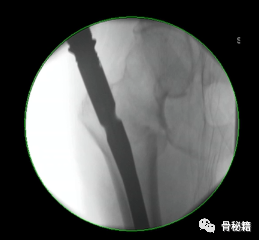

5、钉子的深度。逆行髓内钉的最佳深度是布鲁门萨线的顶点位置,正位居中

近端一般是小粗隆水平以上